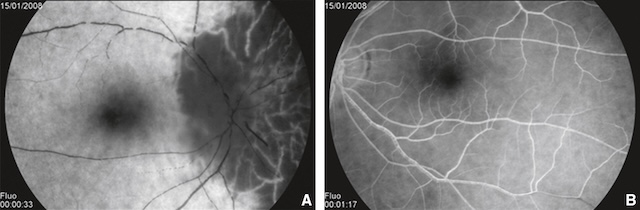

L’angiographie du fond d’œil peut mettre en évidence des signes d’ischémie choroïdienne associée (fig. 16.15) qui sont en faveur d’une origine artéritique (dans le cadre d’une artérite gigantocellulaire : voir plus haut).

A. Large hypoperfusion choroïdienne sans aucune imprégnation de fluorescéine sur l’œil droit. B. Perfusion rétinienne et choroïdienne normale sur l’œil gauche.

Source : S. Milazzo†.

Sur ces deux clichés d’angiographie à la fluorescéine, on observe à l’image A un retard marqué de remplissage artériel au niveau de la tête du nerf optique, associé à une hypofluorescence segmentaire en temporal inférieur. Cette zone sombre indique une absence de perfusion liée à une ischémie sévère. L’image B, prise à un temps plus tardif, montre une diffusion limitée du colorant avec un contraste toujours anormalement faible autour de la papille. Le réseau capillaire périphérique apparaît intact, soulignant le caractère localisé de l’atteinte. Ces éléments traduisent une NOIA artéritique avec obstruction aiguë de la circulation ciliaire postérieure.

297En effet, comme évoqué plus haut, il existe une vascularisation conjointe de la choroïde et de la tête du nerf optique par les ACP. En cas d’artérite gigantocellulaire, l’atteinte est située en amont sur l’artère ophtalmique. Il en résulte un bas débit qui touche toutes les ACP avec une ischémie en aval, de la tête du nerf optique et de la choroïde. Dans la forme non artéritique, l’atteinte est plus localisée sur une ou plusieurs branches d’une ACP avec préservation globale de la vascularisation choroïdienne.